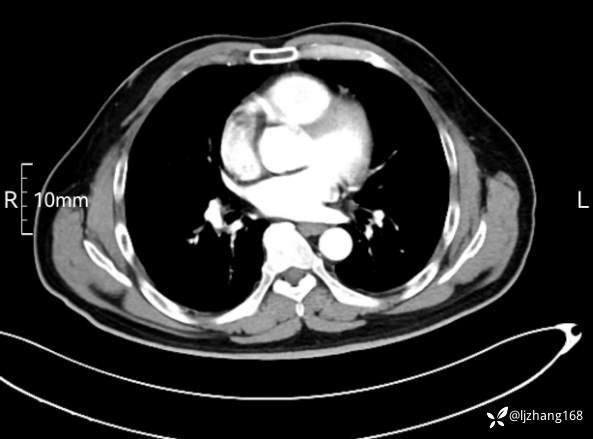

中年男患,右肺团片影,炎症0R肿瘤?

辅助检查:糖化血红蛋白12.3%。肺炎支原体IgG、IgM、呼吸道合胞病毒均未见明显异常。胸部CT:右肺上叶阻塞性肺炎。